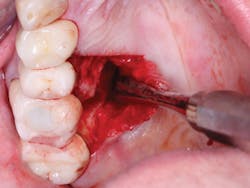

Figure 7: This shows severe postoperative pain caused by removal of large lingual periapical infection on first molar.